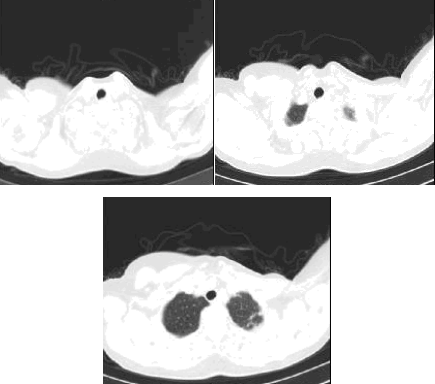

教学流程及学习效果:西安工业大学医学成像技术实验室的PACS实验教学内容主要为了切合生物医学工程专业的教学与科研需求,该实验包括通过影像系统模拟查看人体的各个系统的器官组织的形态、位置和功能,可以进行动态模拟演示的器官(组织)包括脑部结构、心脏动态血流以及主要关节结构等。通过该系统自带视频DSA播放器进行人体器官结构的模拟动态演示,如图所示。

图 利用PACS系统的DSA组件进行脑部结构动态模拟效果